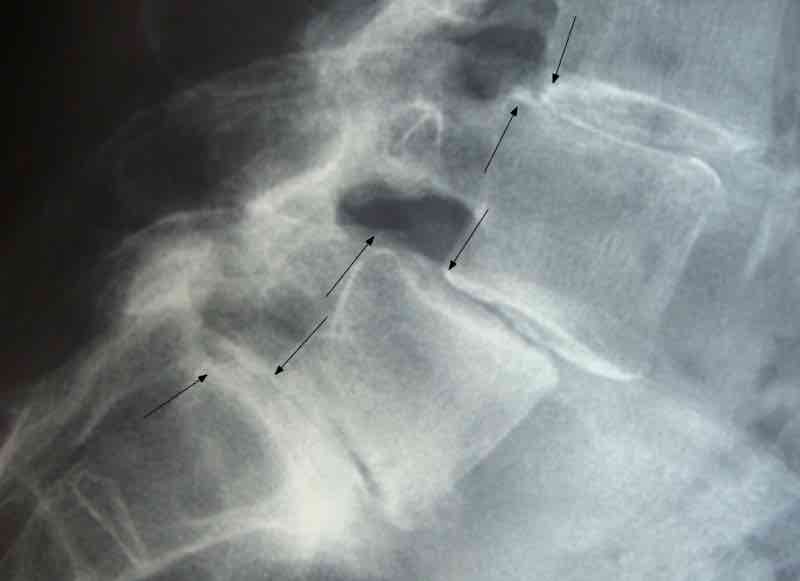

The lumbar facet joints mediate lower back extension.

After a serious slipped disc, the upper vertebra settles lower on its mate below; this means that the facets start to ride on one another causing degenerative change.

The worst that can happen is that the lower facet changes shape to such an extent that it allows the upper vertebra to slide forwards, catching the nerve root in a pincer; it is known as an anterolysthesis. All in all, it is best to mobilise those joints to keep them healthy.